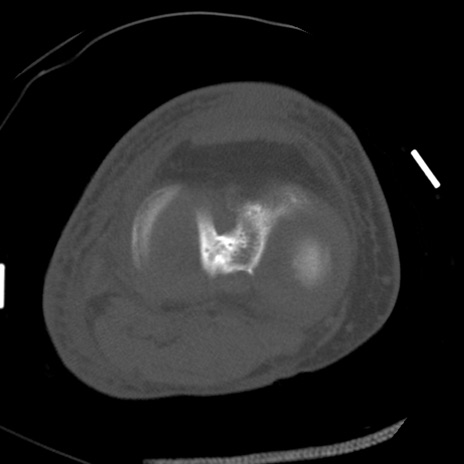

症例28 右膝関節CT(横断像)

右膝関節CT